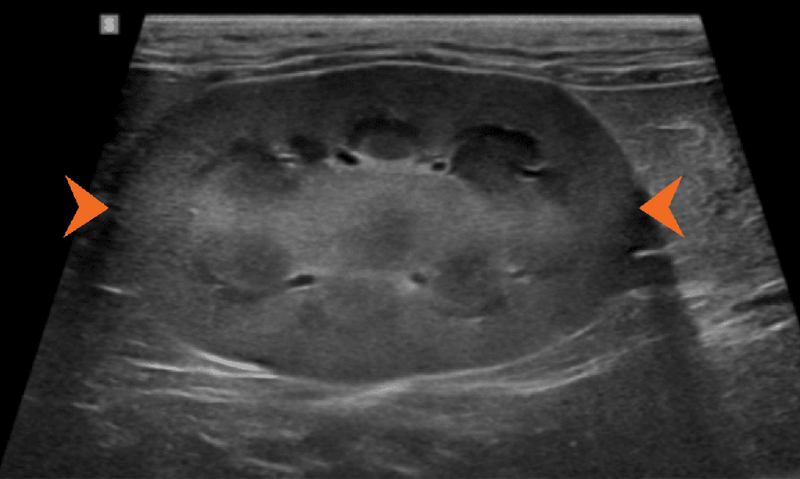

Ryc. 3. Obraz w projekcji strzałkowej lewej nerki kota, przedstawiający wyraźnie zwiększoną echogeniczność kory nerkowej, skutkującą wzmożonym zróżnicowaniem korowo-rdzeniowym, co jest najbardziej zgodne z rozpoznaniem lipidozy kanalikowej. To zjawisko u kotów często powoduje, że nerki są hiperechogeniczne w stosunku do wątroby i/lub śledziony.

Ryc. 4. Obraz w projekcji strzałkowej lewej nerki kota, ukazujący obustronne, słabo odgraniczone obszary hiperechogeniczne w biegunach doczaszkowym i doogonowym (groty strzałek), odpowiadające zjawisku anizotropii.